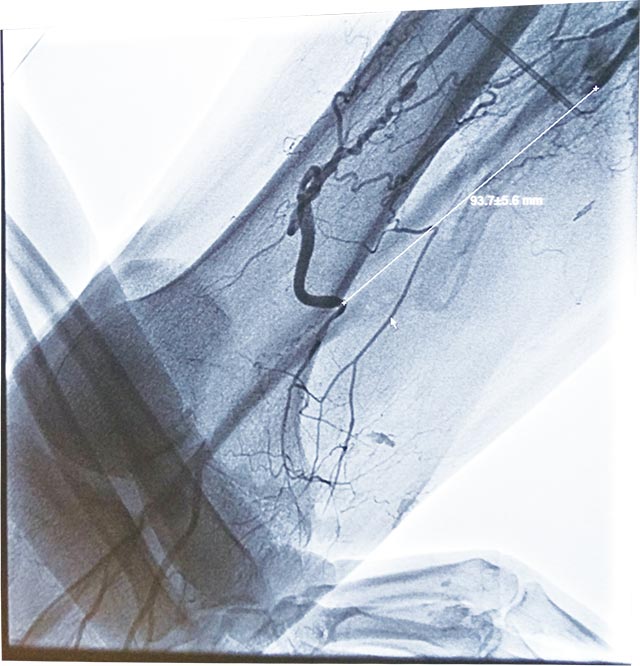

人工血管轉(zhuǎn)流術治療陳舊外傷性右股淺動脈閉鎖 日期:2017-02-23 08:39:00 點擊:2370 好評:36

家住濰坊市臨朐縣的王先生,17年前曾因右下肢外傷曾行二次手術,作股淺動脈自體大隱靜脈搭橋術,術后傷處瘢痕組織明顯。近1年來右足部出現(xiàn)疼痛不適,右踇趾甲床處出現(xiàn)頑固性感染并化膿。輾轉(zhuǎn)多家醫(yī)院就診都...